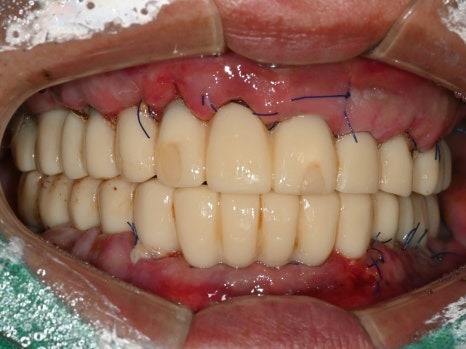

수술 당일

수술 2일 후

직장에서 시간을 내기가 어려우신 상황이라

토요일 오전,

수면마취로 17개의 임플란트를 식립하였고,

월요일에 임플란트 즉시 기능 치아(임시치아)를 끼워드렸습니다.

치료 전

수술 2일후

몇 개월이고 기약 없이 임시 틀니를 써야한다는 걱정에

치료를 시작하지 못하셨던 환자분은

수술 2일 만에 고정된 치아가 완성되자

놀라워하시면서 식사가 가능하게 된 걸

너무 좋아하셨습니다.